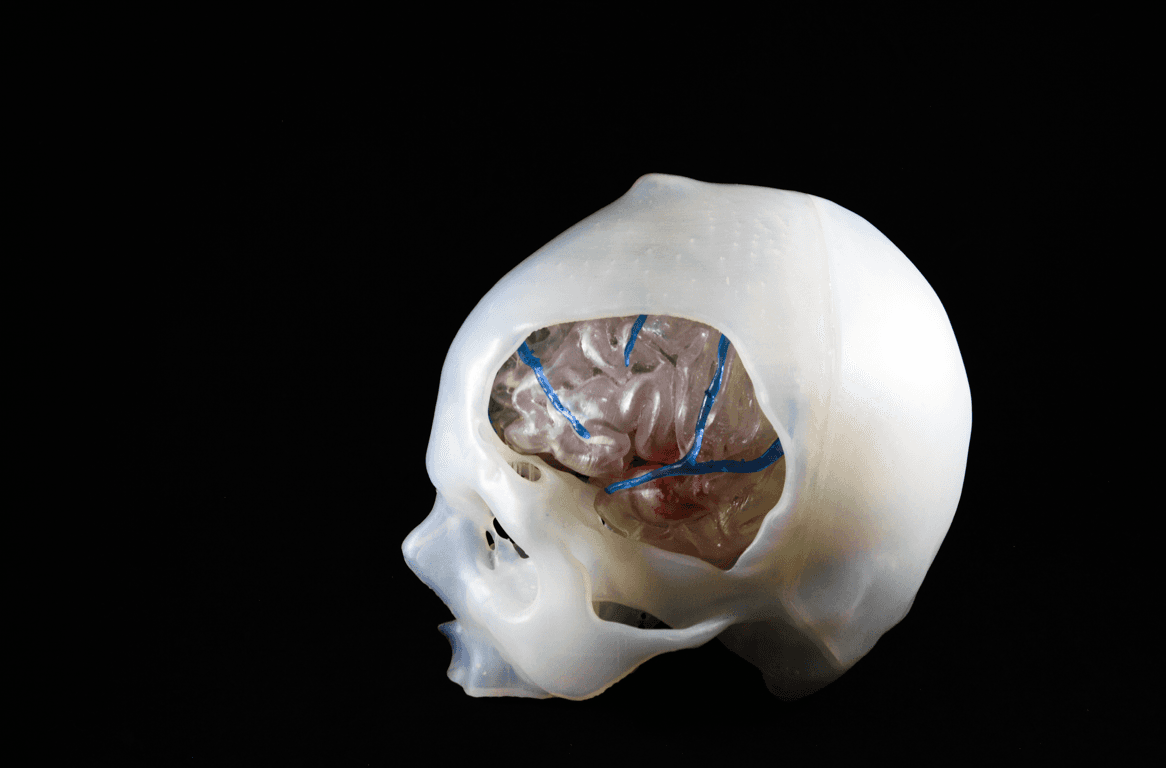

Die Technologie der visuellen 3D-Simulation hat in den letzten Jahren beeindruckende Fortschritte verzeichnet. Für viele Operationsteams haben jedoch physisch greifbare Modelle und die Möglichkeit, Eingriffe an einem maßgefertigten Modell üben zu können, einen noch größeren positiven Einfluss auf die Operationsergebnisse. Die mehrschichtigen, segmentierten und vollständig integrierten Modelle von TrabTech können bei Kraniotomien eine Hilfe bieten. Hierbei müssen die Operierenden nämlich in den Schädel bohren und zur Zugangsbildung einen Teil davon ausschneiden – ein Vorgang, der sich Fenestrierung nennt –, ohne dabei das darunterliegende Gewebe zu verletzen.

Das individuelle Modell erlaubt es dem OP-Team nicht nur, die Anatomie zu visualisieren, sondern auch den Eingriff zu simulieren. So erhalten Chirurg*innen die Chance, den operativen Eingriff im Vorhinein zu üben und verschiedene Herangehensweisen an die Behandlung der Pathologie zu testen. Dadurch können sie die Vor- und Nachteile bestimmter Operationstechniken überblicken und Hindernisse erkennen.

3D-gedruckter Schädel, in dem Gehirn und Arterien sichtbar sind, zur Übung von Kraniotomien.

Das Gute an 3D-gedruckten Modellen ist, dass das Gehirn transparent dargestellt werden kann, sodass das Aneurysma und die Gefäße unter dem Temporal- und Frontallappen leicht sichtbar sind. Die Bedeutung physischer 3D-gedruckter Modelle im Vergleich zu digitalen 3D-Modellen wird offensichtlich, wenn das OP-Team nicht über die erforderliche Erfahrung für einen Eingriff verfügt. Hier kann ein 3D-gedrucktes Modell helfen, die Position eines Aneurysmas und die Kraniotomie zu standardisieren.

Zwar lassen auch digitale 3D-Modelle es zu, virtuelle Segmentierungen und Anpassungen wie etwa Positionsänderungen durchzuführen, aber das haptische Feedback fehlt. Mit 3D-gedruckten Modellen erhalten Chirurg*innen verschiedene Blickwinkel auf das Gehirn. Wurde das Modell jedoch einmal beschädigt oder zerschnitten, lässt sich das nicht mehr rückgängig machen.